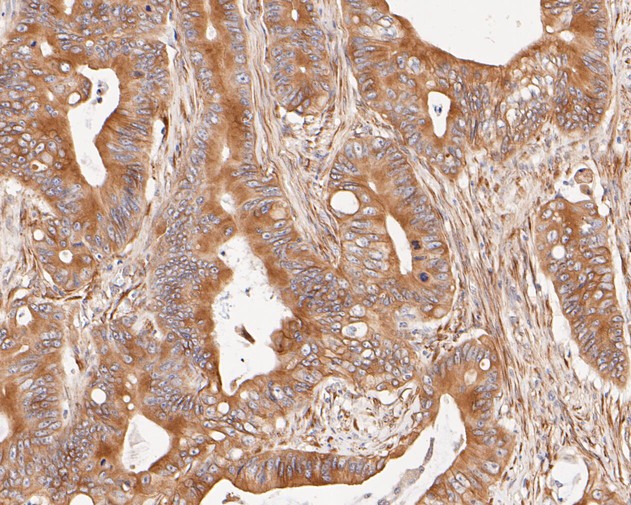

|   | Fig2: Immunohistochemical analysis of paraffin-embedded human small intestine tissue using anti-Cytokeratin 20 antibody. The section was pre-treated using heat mediated antigen retrieval with Tris-EDTA buffer (pH 8.0-8.4) for 20 minutes.The tissues were blocked in 5% BSA for 30 minutes at room temperature, washed with ddH2O and PBS, and then probed with the primary antibody (EM1901-96, 1/400) for 30 minutes at room temperature. The detection was performed using an HRP conjugated compact polymer system. DAB was used as the chromogen. Tissues were counterstained with hematoxylin and mounted with DPX. |